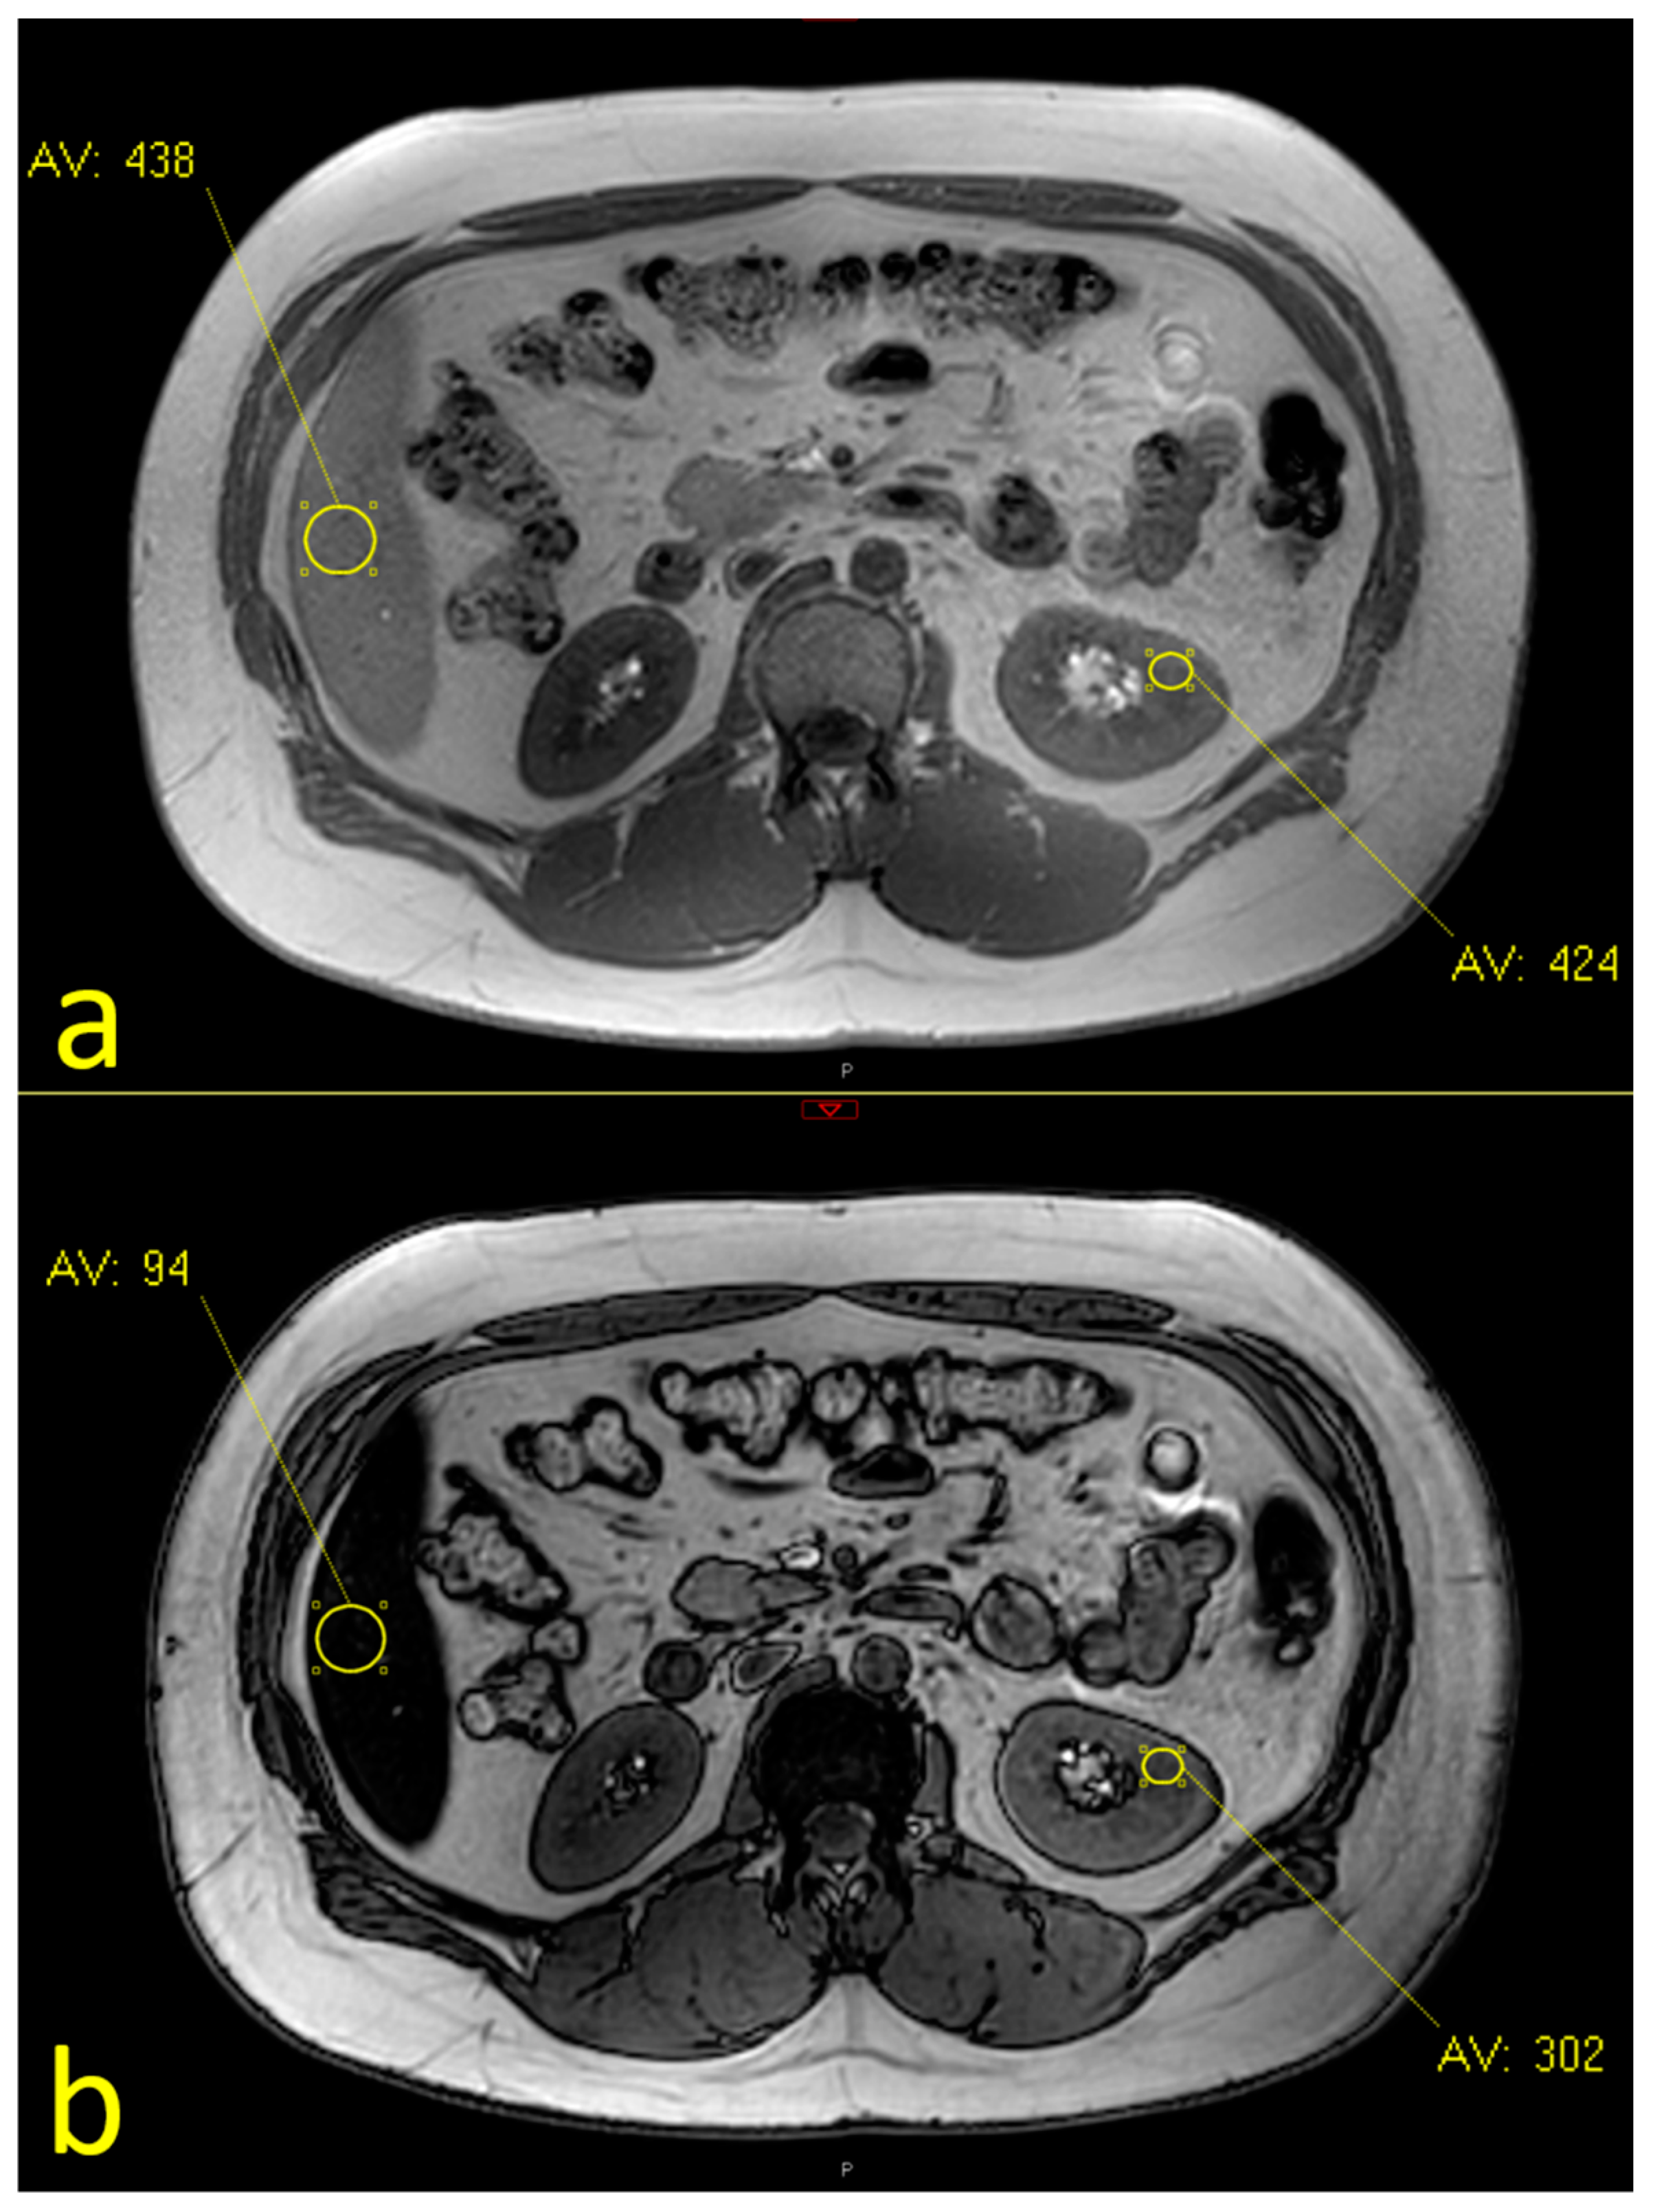

2.2. MRI Assessment